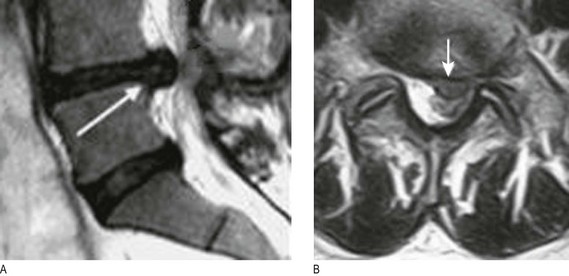

Fig. 11.27 Patterns of sensory loss.

(A) In length dependent peripheral neuropathy. (B) Brown-Séquard syndrome. Note the distribution of corticospinal, posterior column and lateral spinothalamic tract signs. The cord lesion is in the left half of the cord.